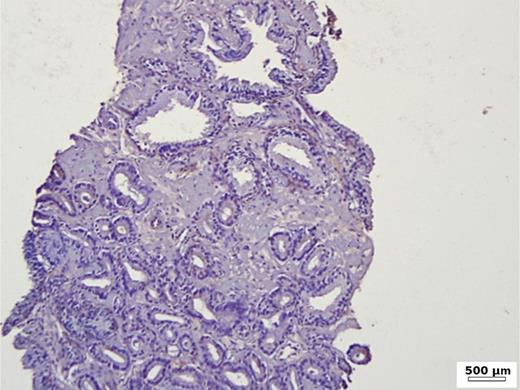

In the group of patients without carcinoma, the vast majority exhibited BSP expression of less than 1%. Twenty-nine out of thirty patients had a value below 5% (Table 1). One patient showed a BSP expression of 9%; however, the expression was observed only in basal cells in a condition of basal cell hyperplasia combined with chronic inflammation (Fig. 1). BSP expression in prostate tissue without carcinoma and without basal cell hyperplasia is shown in Figure 2.